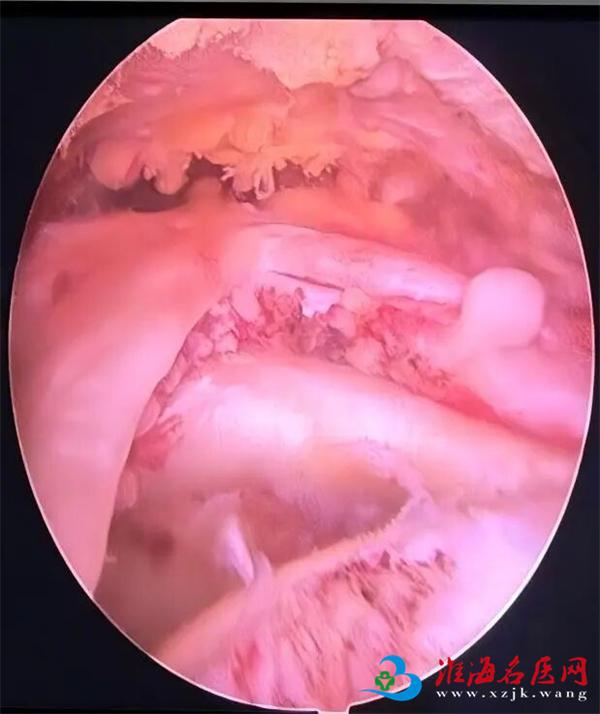

以往,治疗肩袖损伤往往需要大面积切开肩膀进行开放手术,这不仅创伤大、恢复慢,还可能留下明显的疤痕。如今,随着医疗技术的进步,关节镜下肩袖修补术已成为主流和首选方法。这项技术仅需在肩部开3-4个如“钥匙孔”般微小的切口(约1厘米),然后伸入高清微型摄像头(关节镜)和精密手术器械,医生通过监视器放大清晰的影像进行操作,精准地对撕裂的肌腱进行修复和固定。

视野清晰,处理精准。 高清镜头可将关节内结构放大数十倍,使手术视野更清晰,能发现X光、MRI难以显示的隐匿损伤,并进行精准修复。

一次手术,全面诊断。 关节镜技术在修补肩袖的同时,还能全面检查并处理肩关节内的其他并存问题,如肩峰成形、清理增生滑膜等。